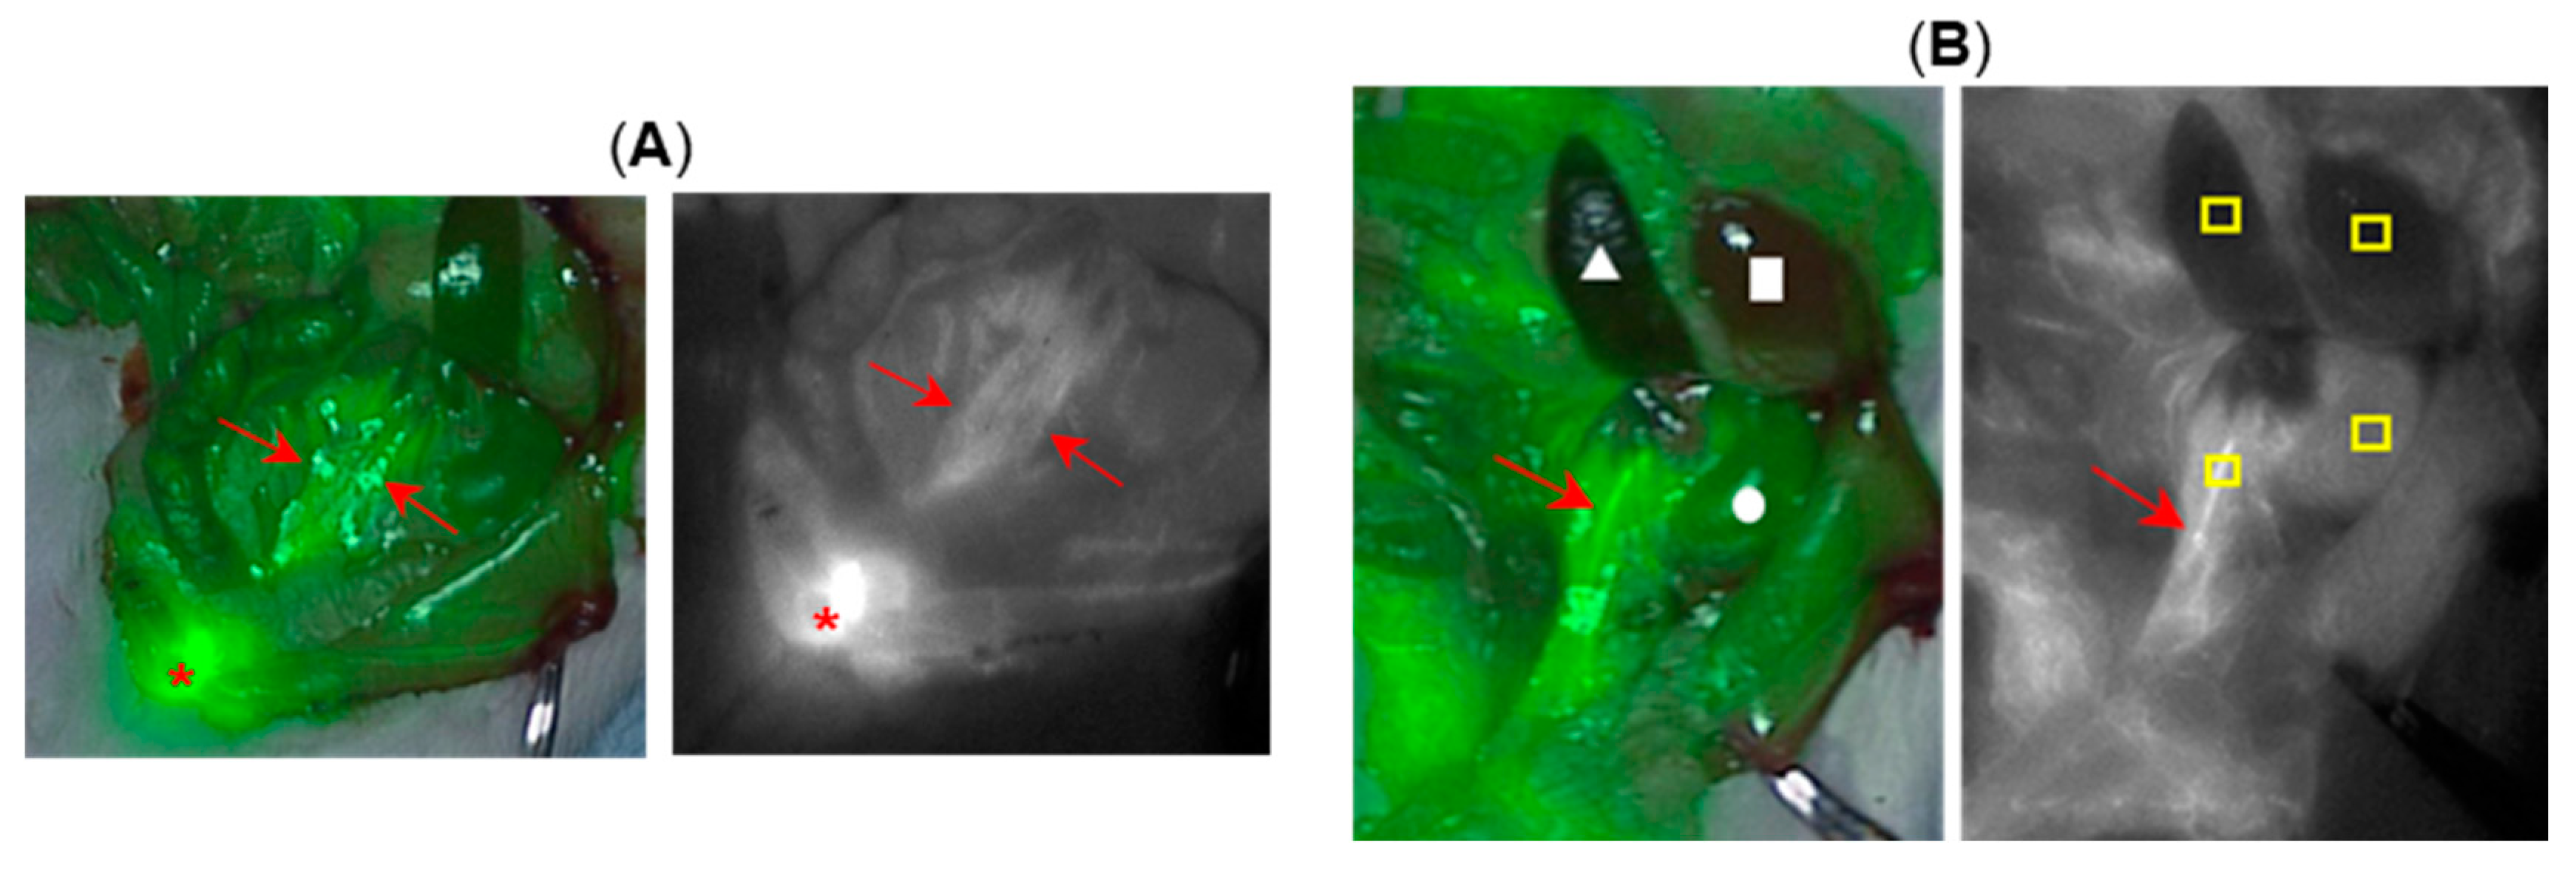

Next, surgical exposure of the lower abdomen was carried out prior to fluorophore administration such that direct observation of the ureters and other abdominal organs was possible. Fluorophore 12 was selected for this study being administered at a dose of 0.5 mg/kg with imaging continued for 90 min. Immediately following the tail vein injection, the blood vessel fluoresced with the kidneys also becoming fluorescent within seconds which was sustained throughout the 90 min (SI Figure S6). In each animal the ureters were identifiable within 20 min post administration and this maintained throughout the 90 min imaging period. A representative image (displayed both as fluorescence pseudo coloured green overlaid on the white light image and as fluorescence alone in black and white) is shown in Figure 6 panel A which was recorded after 35 min. In this image, both ureters (red arrows) are visible as is the highly emissive bladder (asterisk) (see SI movie S1). A clear predisposition of fluorescence from the kidneys relative to the liver and other organs existed throughout, confirming the preference for renal clearance of 12. A representative example of this is shown in Figure 6 panel B which was recorded 50 min post administration. In this case the animal was positioned to allow a clearer view of one ureter (red arrow), a kidney (circle), spleen (triangle) and liver (square) such that a relative fluorescence intensity quantification could be carried out for each organ (Figure 6, panel B, left). An averaged pixel intensity was determined for four regions of interest of the ureter, kidney, spleen and liver as indicated by the yellow boxes (panel B, right). The emission ranged from highest to lowest for the ureter >> kidney >> liver > spleen with ratio intensity values of 4.8:2.8:1.1:1, respectively (Figure 6B, SI Figure S7 for pixel analysis data).

Figure 6.

Representative imagery from surgical rat model study showing exposed ureters (n = 3). (A) Image recorded at 35 min post-administration of 12. Left, fluorescence (pseudo coloured green) overlaid on white light image. Right, fluorescence alone shown as black and white for clarity. Both ureters indicated by red arrows and bladder by asterisk. (B) Image recorded at 50 min. Left, fluorescence (pseudo coloured green) overlaid on white light image, red arrow (ureter), circle (kidney), triangle (spleen), square (liver). Right, fluorescence alone shown as black and white for clarity. Red arrow identifying ureter and yellow boxes indicate regions from which the average pixel intensity data were obtained.